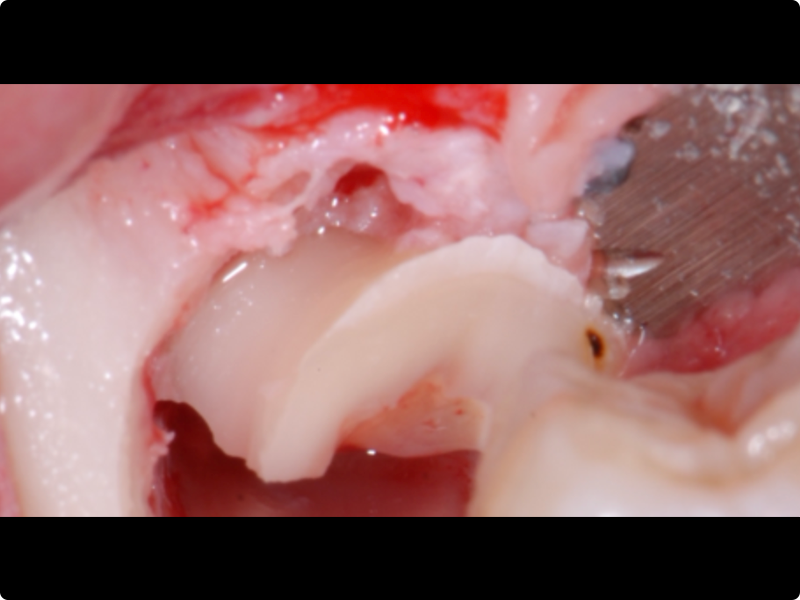

- Odontotomy and rhizotomy.

- Dislocation and extraction.

Clinical cases of impacted third molar surgery and explanatory videos

- Traditional technique exercises with rotary burs (teeth kit by Dr. A. Borgonovo).

- Sonic technique exercises with inserts dedicated to the surgery of impacted teeth.